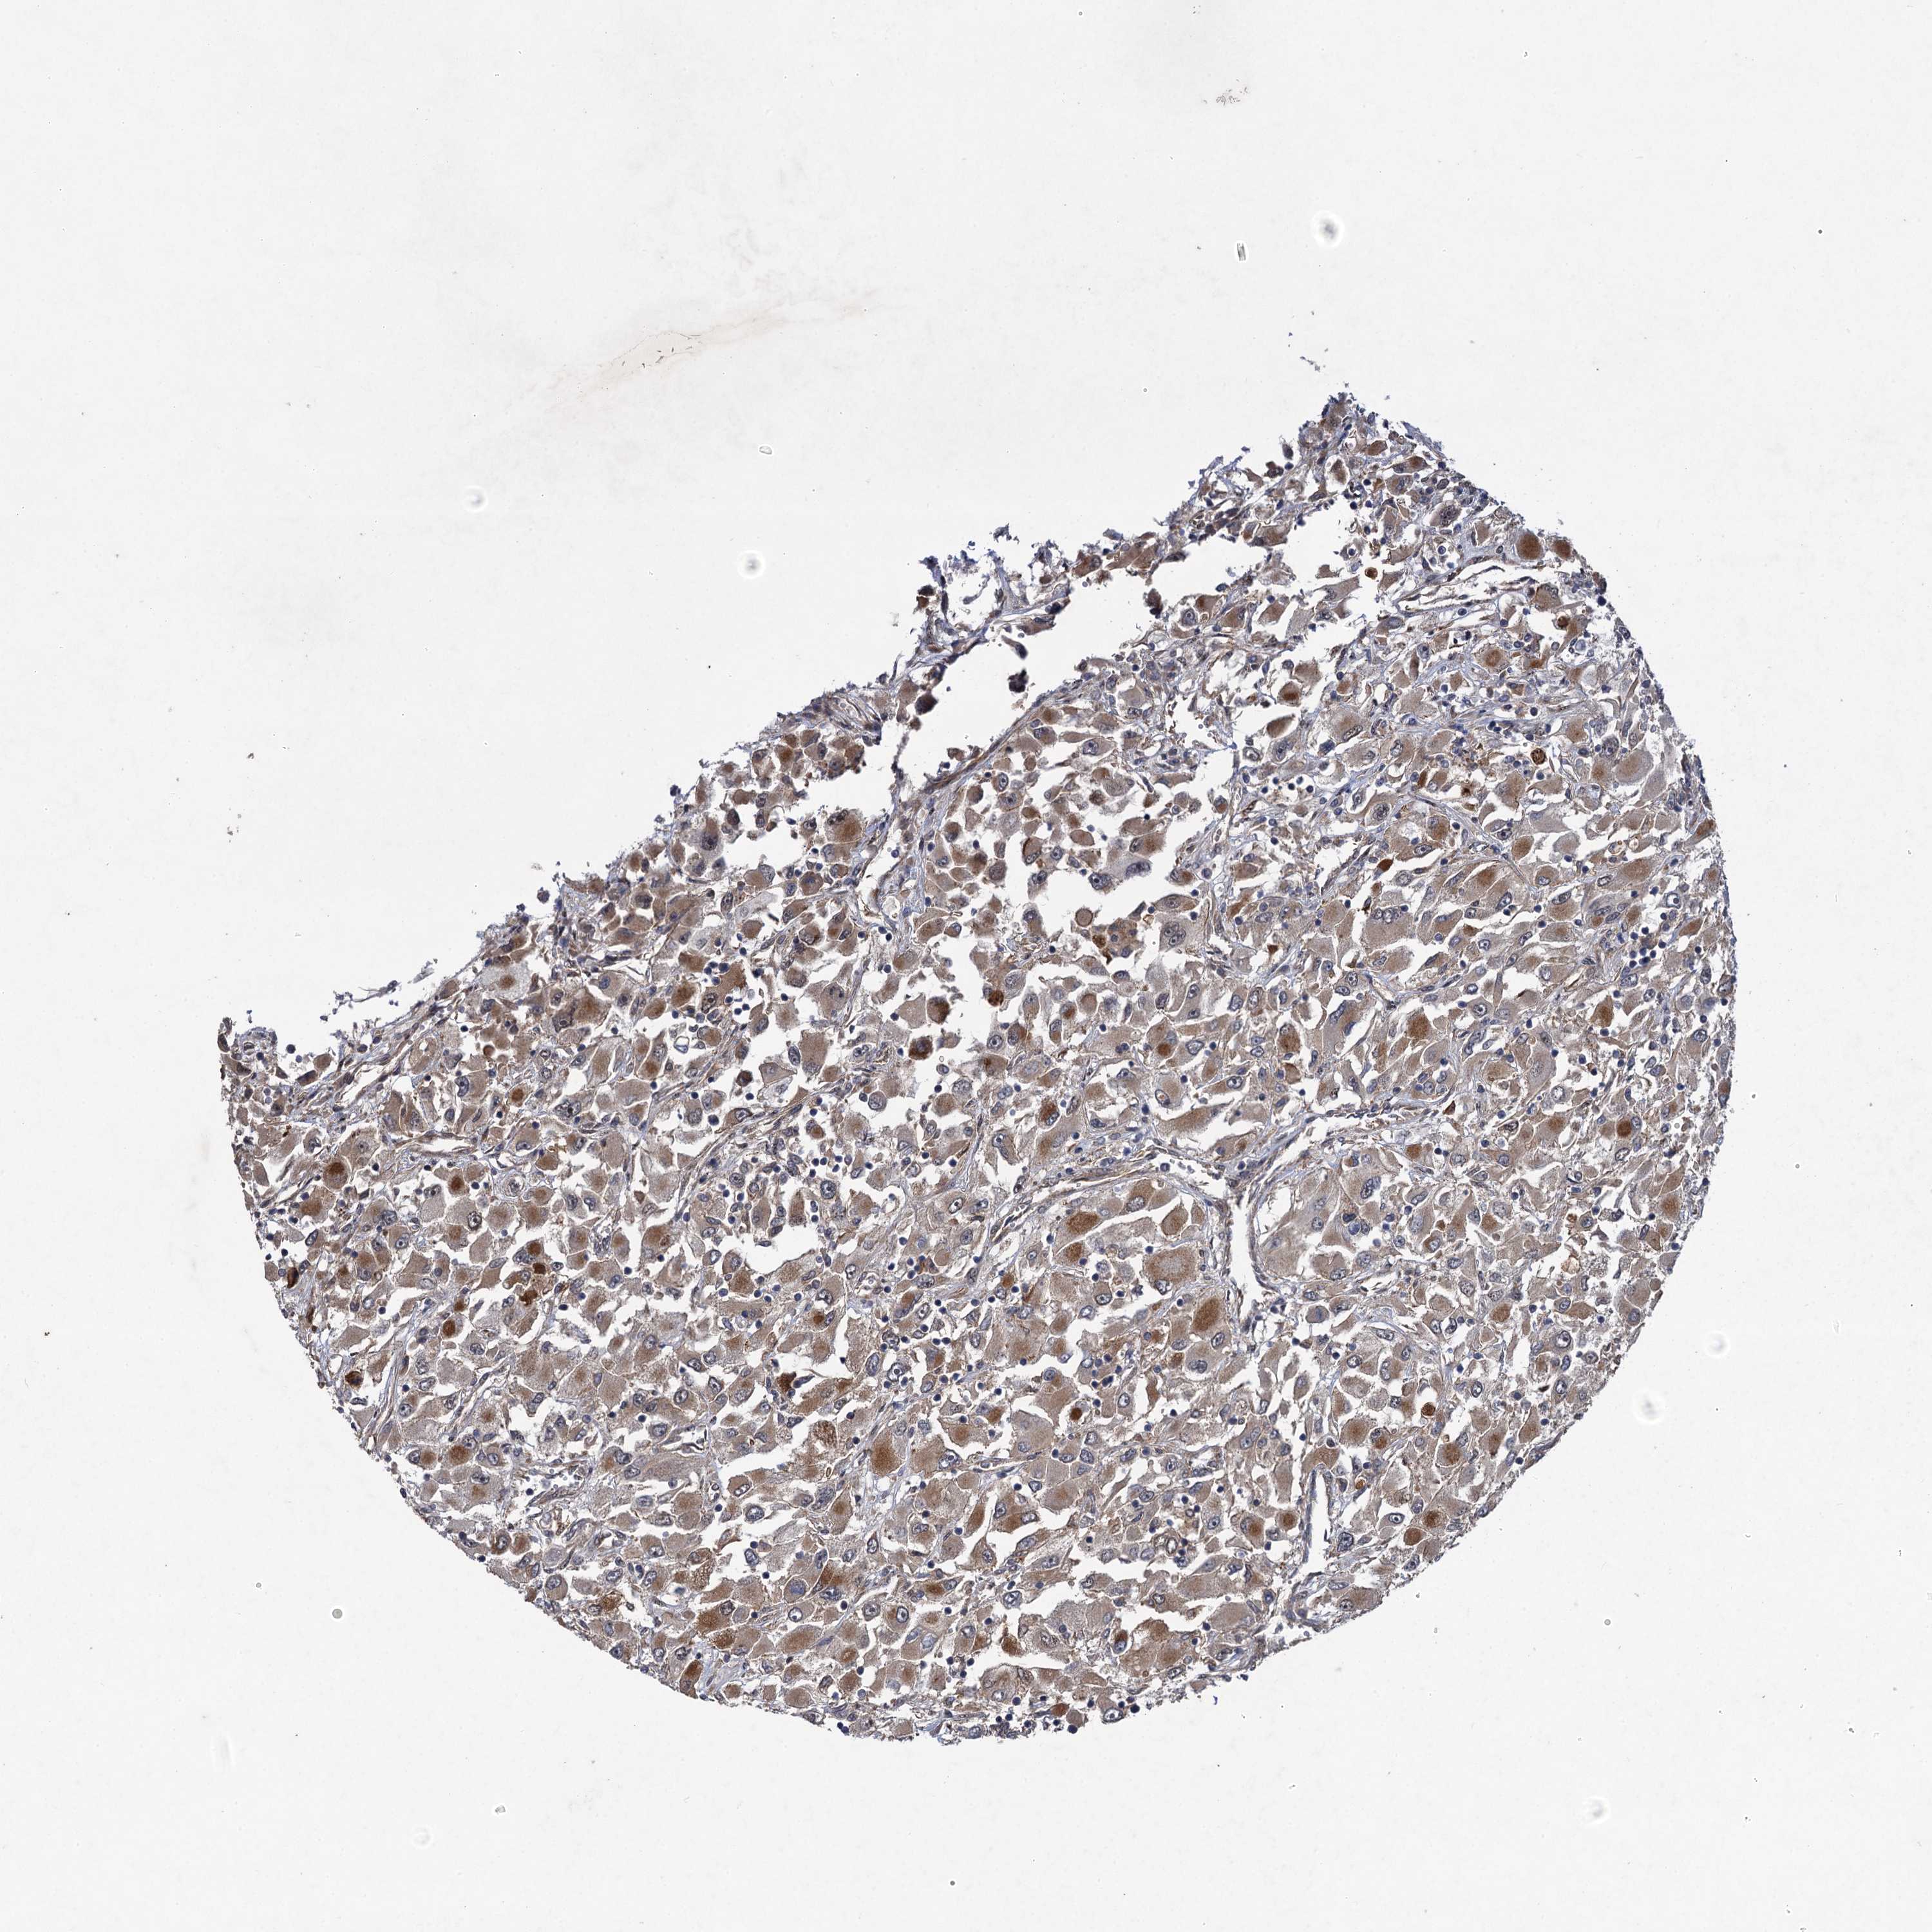

KIDNEY RENAL CLEAR CELL CARCINOMA (VALIDATION) - Interactive survival scatter ploti

The Survival Scatter plot shows the clinical status (i.e. dead or alive) for all individuals in the patient cohort, based on the same data that underlies the corresponding Kaplan-Meier plots. Patients that are alive at last time for follow-up are shown in blue and patients who have died during the study are shown in red.

The x-axis shows the expression levels (FPKM) of the investigated gene in the tumor tissue at the time of diagnosis. The y-axis shows the follow-up time after diagnosis (years). Both axes are complimented with kernel density curves demonstrating the data density over the axes. The top density plot shows the expression levels (FPKM) distribution among dead (red) and alive patients (blue). The right density plot shows the data density of the survived years of dead patients with high and low expression levels respectively, stratified using the cutoff indicated by the vertical dashed line through the Survival Scatter plot. This cutoff is automatically defined based on the FPKM cutoff that minimizes the p-score. The cutoff can be changed by dragging the vertical line or by entering a cutoff value in the square labeled "Current cut-off".

Under the Survival Scatter plot the p-score landscape (black curve; left axis) is shown together with dead median separation (red curve; right axis). Dead median separation is the difference in median mRNA expression between patients who have died with high and low expression, respectively. It is calculated as follows: median FPKM expression of dead patients with high expression - median FPKM expression of dead patients with low expression. This is intended to aid the user in visually exploring custom cutoffs and the associated p-scores and dead median separation.

Individual patient data is displayed and can be filtered by clicking on one or more of the category buttons on the top of the page. Categories describing expression level and patient information include: high, low, alive, dead, female, male and tumor stages. The scale of the x-axis can be toggled between linear and log-scale by clicking on the "x log" button. Mouse-over function shows TCGA ID, patient information and mRNA expression (FPKM) for each patient.

& Survival analysisi

Kaplan-Meier plots summarize results from analysis of correlation between mRNA expression level and patient survival. Patients were divided based on level of expression into one of the two groups "low" (under cut off) or "high" (over cut off). X-axis shows time for survival (years) and y-axis shows the probability of survival, where 1.0 corresponds to 100 percent.

HAUS1 is not prognostic in Kidney Renal Clear Cell Carcinoma (validation)

Best expression cut offi

Based on the FPKM value of each gene, patients were classified into two groups and association between prognosis (survival) and gene expression (FPKM) was examined. The best expression cut-off refers the FPKM value that yields maximal difference with regard to survival between the two groups at the lowest log-rank P-value. Best expression cut-off was selected based on survival analysis .

When clicking on this number, the vertical dashed line indicating cut-off, the interactive survival plot, and the Kaplan-Meier curve will be adjusted to show results based on the best expression cut-off.

: 22.86

P scorei

Log-rank P value for Kaplan-Meier plot showing results from analysis of correlation between mRNA expression level and patient survival.

N/A

Average pTPM 19.7

Number of samples 100